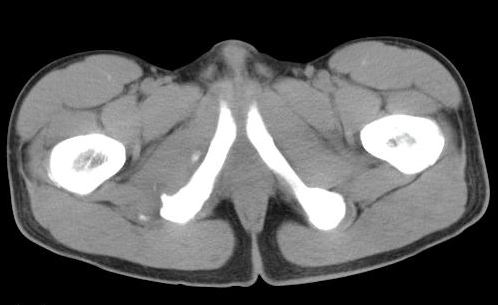

男性,15岁,半年前曾有做运动摔伤史,伤后左肢麻木,一天后恢复,两个月后因右臀部隐痛照片示右坐骨下骨性密度影,现复查见骨性影无明显改变。求助诊断!

支持坐骨撕脱性骨折合并血肿机化、骨化。

坐骨骨折,血肿机化

坐骨陈旧性撕脱性粉碎性骨折伴骨痂形成.